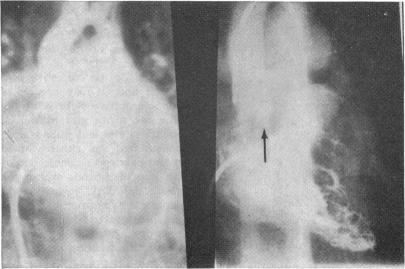

Congenital heart disease--changes in form and function.

Br Heart J. 1979 Jan;41(1):1-22. doi: 10.1136/hrt.41.1.1.